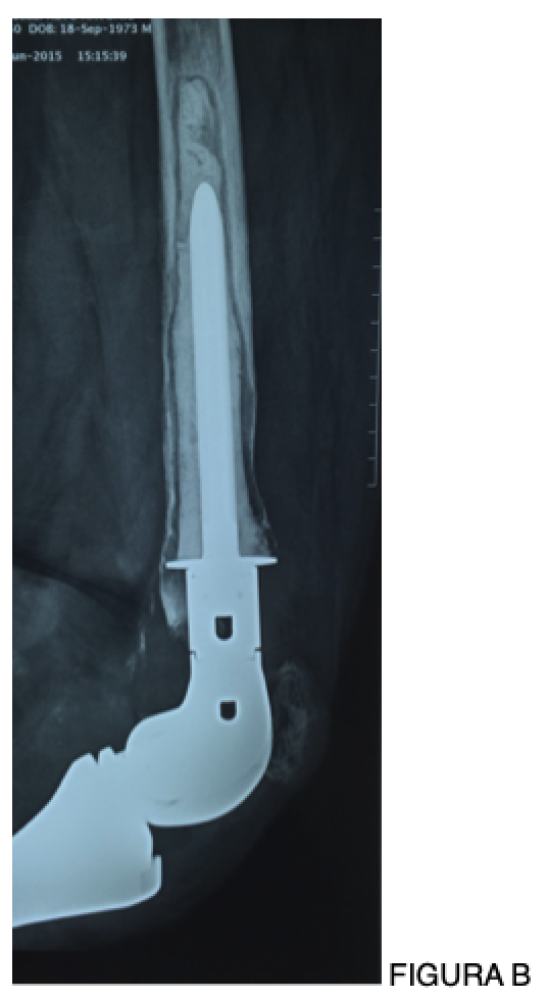

Sequenciamento genético de nova geração (NGS – Next-Generation Sequencing) permite a detecção do DNA bacteriano diretamente no líquido aspirado da articulação, com maior sensibilidade, especialmente em infecções cultura-negativas ou parcialmente tratadas [11].

É importante ressaltar que o sequenciamento genético do DNA da bactéria já está disponível em nosso meio, podendo ser solicitado em centros especializados, e representa hoje o método mais sensível para identificação do agente etiológico nos casos complexos.